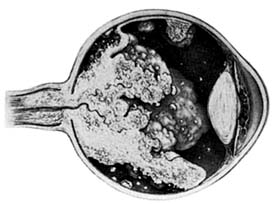

Figure 10-30

Figure 10-30: Angiomatosis retinae of Von Hippel-Lindau disease (drawing). (Courtesy of F Cordes.)

Retinal hemangiomas occur as isolated tumors or associated with cerebellar hemangioblastomas, pancreatic cysts and carcinomas, renal cysts and carcinomas, and pheochromocytomas in von Hippel-Lindau syndrome (Figure 10-30). The retinal tumors are pink or red, endophytic, and usually supplied by a large feeder vessel. Juxtapapillary tumors are usually exophytic. Vision is affected by bleeding or exudation from the tumor vessels. Photocoagulation, diathermy, and cryotherapy are used to treat the retinal lesions.